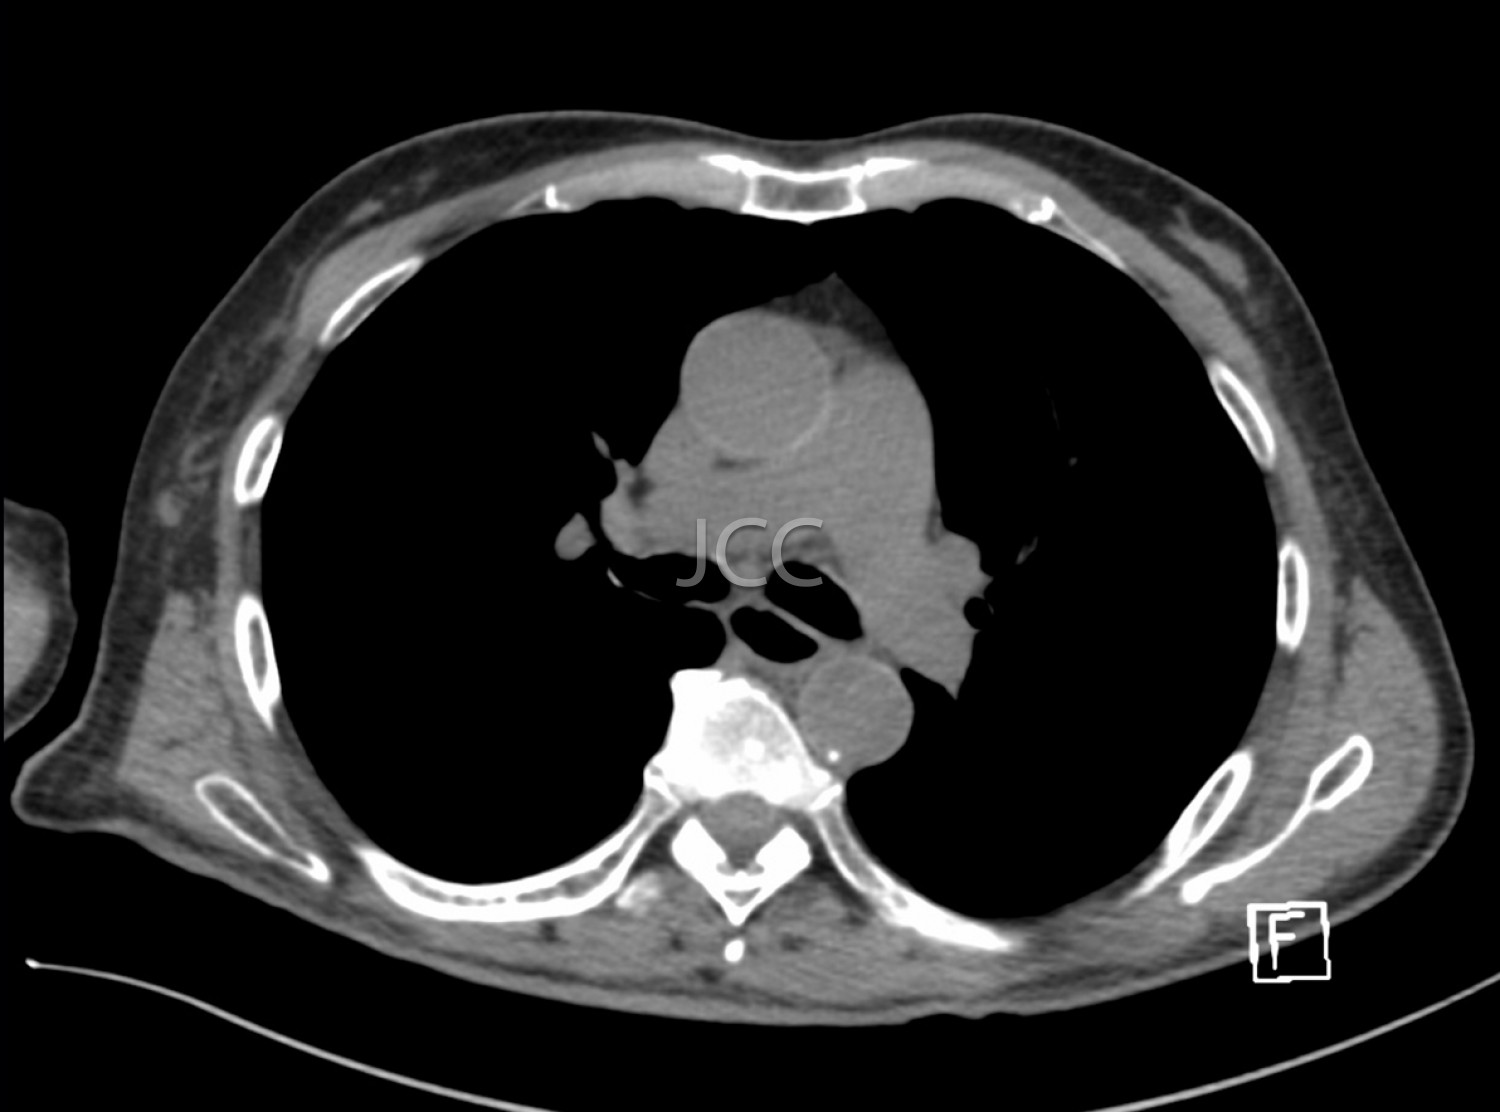

Computed Axial Tomography - Thoracic

Computed Axial Tomography (CAT) - Dual Energy - 256 slices is a diagnostic technique that allows the evaluation of various parts of the human body, including the lungs, liver, pancreas, kidneys, heart, vascular structures and bone structures.